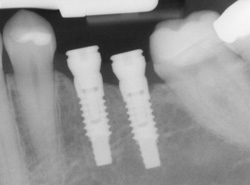

Implants X-raySingle or Multiple Implants

Implants are versatile. If you are only missing one tooth, one implant plus one replacement tooth will do the trick. If you are missing several teeth in a row, a few strategically placed implants can support a permanent bridge (a set of replacement teeth). Similarly, if you have lost all of your teeth, a full bridge or full denture can be permanently fixed in your mouth with a strategic number of implants.